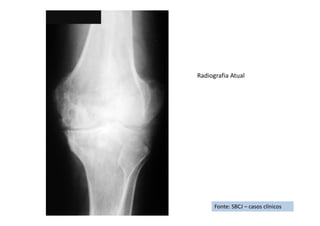

Fonte: SBCJ – casos clínicos

RX de Frente

RX de Perfil